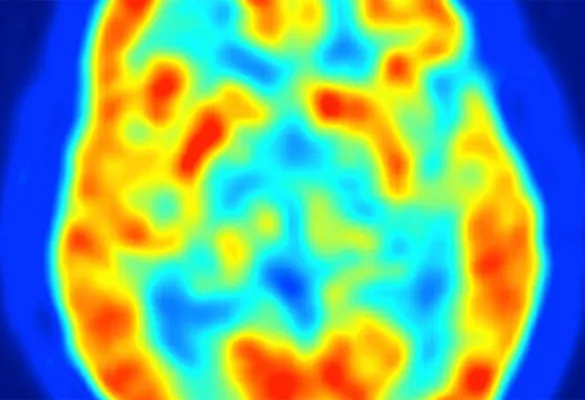

PET MRI

2015

For the first time in the US, full-body, simultaneous time-of-flight PET/MRI became available at UCSF. This state-of-the-art dual imaging technology reduces radiation, enhances image quality, and is safer and more convenient for patients.